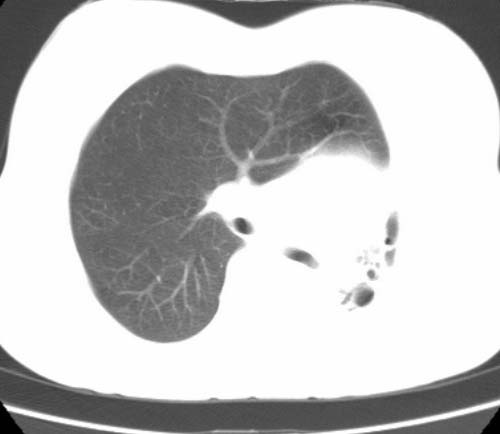

标题: CT25648:求教:是肺发育不全还是结核?

女  20岁。一月前咳血,诊“肺结核”抗痨治疗一月后,咳血停止,现复查。病人精神好。前后ct片对比未见明显变化。既往体检“正常”

1)考虑左肺结核并肺不张、支气管扩张。2)纵隔疝。

考虑左肺结核,左肺毁损,纵膈左偏,既往体检正常不可靠,tb一个月也不会这个样子的,有钙化,应该病程较长,冰冻三尺非一日之寒!

左肺发育不全。

考虑左肺结核,左肺毁损,纵膈左偏,既往体检正常不可靠,tb一个月也不会这个样子的,有钙化,应该病程较长,冰冻三尺非一日之寒

结核,左肺毁损。